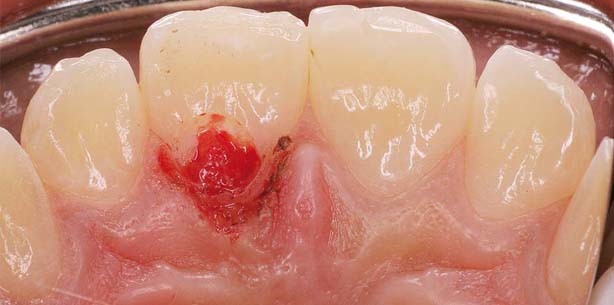

Vier Jahre nach dem Unfall im Mai 2007 zeigte sich bei einer Routineuntersuchung dann eine externe Resorption palatinal marginal am Zahn 11 (Abb. 1–3). Alle anderen Zähne waren vital und unauffällig. Der Zahn 11 war schmerzfrei, reagierte auf Kälte negativ. Im Röntgenbild stellte sich eine große zervikale und apikale Aufhellung dar (Abb. 3 und 7). Nach Reduktion der marginalen Gingiva mittels Elektrotom und vorsichtiger Eröffnung der Resorptionshöhle sah man im Defekt stark durchblutetes Gewebe (Abb. 4). Als dieses grob entfernt war, sah man das offene Pulpenkavum mit devi­taler Pulpa (Abb. 5). Das Pulpenkavum wurde grob ge­reinigt und dann eine medikamentöse Einlage mit Ledermix vorgenommen. Der Verschluss erfolgte mit Cavit und Glasionomer-Zement (GIZ; Abb. 6 und 7).